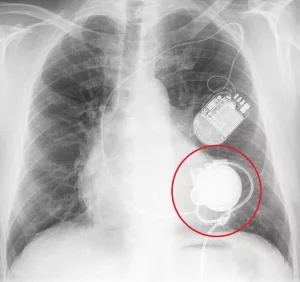

Das auf dem Röntgenbild erkennbare Kunstherz wurde in die linke Herzkammer eingesetzt und pumpt das Blut von dort in die Aorta. Darüber erkennt man einen Kardioverter-Defibrillator, der wegen lebensbedrohlichen Herzrhythmusstörungen zusätzlichen eingesetzt wurde.

Die Implantate sind über Kabel mit einer externen Kontrolleinheit und der Stromversorgung, meist zwei separaten Batteriepacks, verbunden.